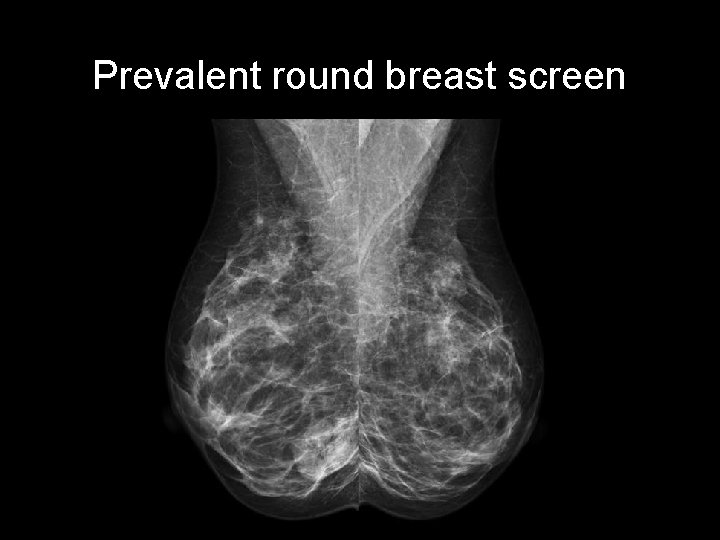

Prevalent round breast screen

Prevalent round breast screen • Round lobulated right breast mass with sharp outline and halo • Lucent lines within the mass due to air within the lesion SKIN LESION: NAEVUS http: //radiopaedia. org/cases/breast-naevus